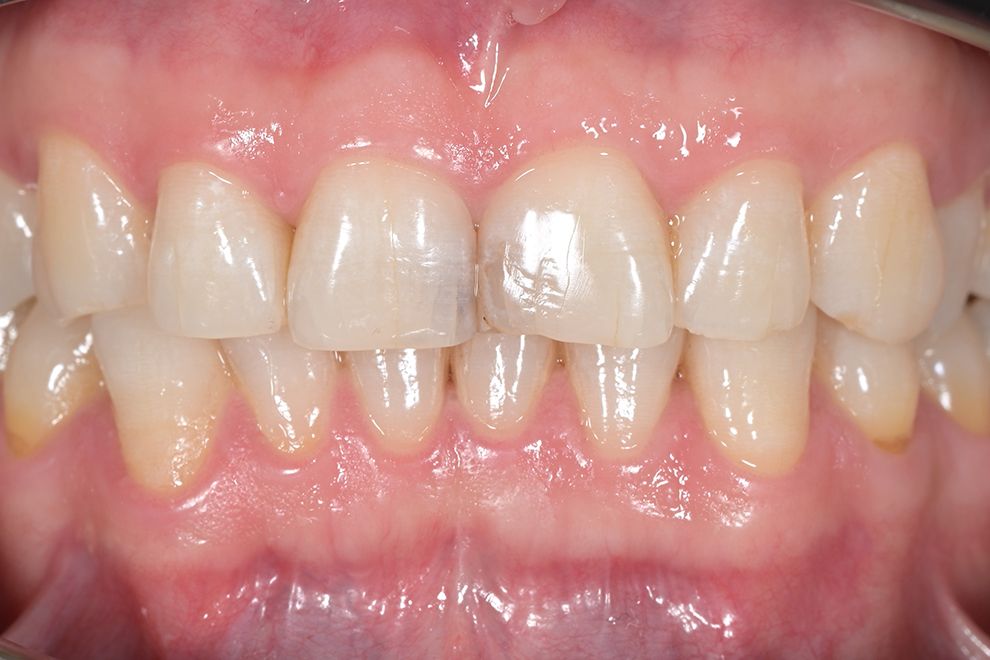

до и после